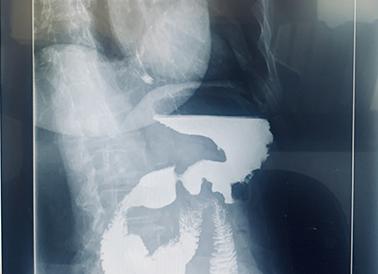

Что показывает рентген кишечника с барием?

Рентген желудочно-кишечного тракта с применением контраста − взвеси бария (вещества, которое задерживает рентгеновские лучи), показывает:

• моторную функцию кишечника;

• эластичность стенок кишки;

• смещаемость, внешние контуры кишки;

• наличие язвенных дефектов, колитов;

• есть ли рак, полипы. опухоли;

• дивертикулы;

• инвагинацию;

• патологические сужения;

• непроходимость.

Рентгенограмма тонкой кишки с сернокислым барием: хорошо видны физиологические Кернинговы складки слизистой оболочки

Делают рентген кишечника с сернокислым барием под контролем рентген телевизионного просвечивания. Исследование сопровождается высокой лучевой нагрузкой на пациента. Его применение обусловлено необходимостью выявления серьезной жизнеугрожающей патологии (язва или рак толстого кишечника).

Контрастная рентгенография желудочно-кишечного тракта показывает:

• моторную функцию толстого кишечника;

• эластичность, смещаемость, внешние контуры кишки;

• язвенные дефекты, рак, полипы, дивертикулы;

• толстотонкокишечные свищи.